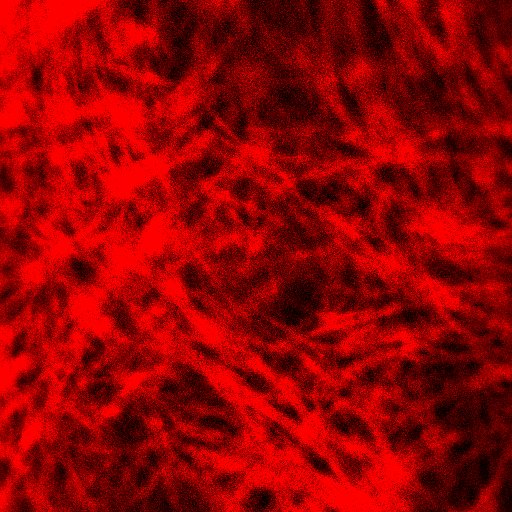

- 胶原纤维成像:SHG通道可直观显示胶原纤维的密度和排列变化,评估抗皱产品的功效。

图10. SHG通道胶原纤维—平面图像

图11. SHG通道胶原纤维—立体图像

注:

- 胶原纤维属于功能性蛋白质,较粗大,直径1~20μm成束状分布,排列紧密,并交织成网状。

- 双光子胶原纤维的扫描可观察深度一般为40μm,甚至更深。

- 可以在二次谐波通道观察到胶原纤维(红色),平面图像主要特征为纹理结构,呈现条带状或网状,立体图像由于不同深度的胶原纤维叠加,主要呈现为立体网状或蓬松的云状结构。